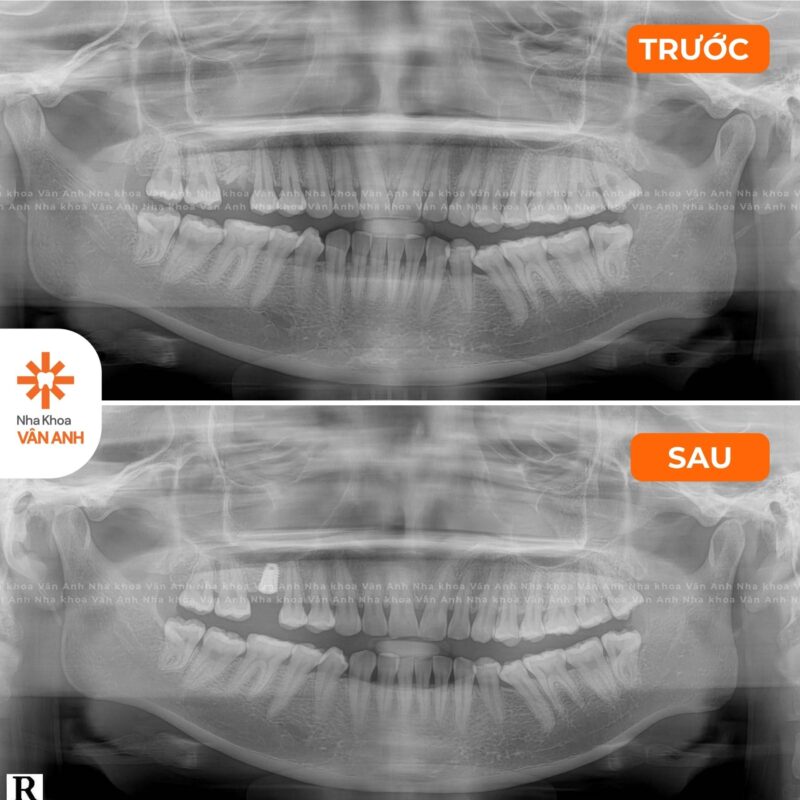

Lĩnh vực chuyên sâu: Phục Hình – Tiểu Phẫu

- Chứng chỉ Cắm Ghép Implant Nha Khoa – Viện Đào tạo Răng Hàm Mặt, Đại học Y Hà Nội.

- Chứng nhận đào tạo Cấy ghép implant Nha khoa nâng cao: Implant tức thì và Implant vùng thẩm mỹ – Viện Đào tạo Răng Hàm Mặt, Đại học Y Hà Nội.